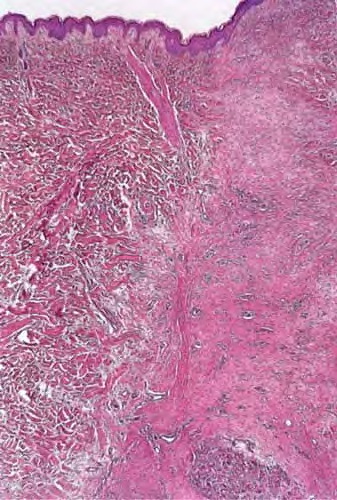

Suture granuloma = الحبيبوم مكان الغرزة الجراحية